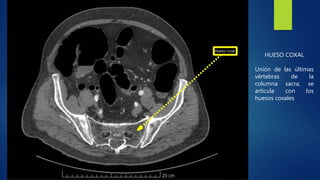

El documento describe brevemente cinco partes del cuerpo humano: el hígado, el riñón derecho, la articulación costovertebral, el hueso coxal y la cabeza del fémur. Se proporciona una función clave de cada parte del cuerpo.